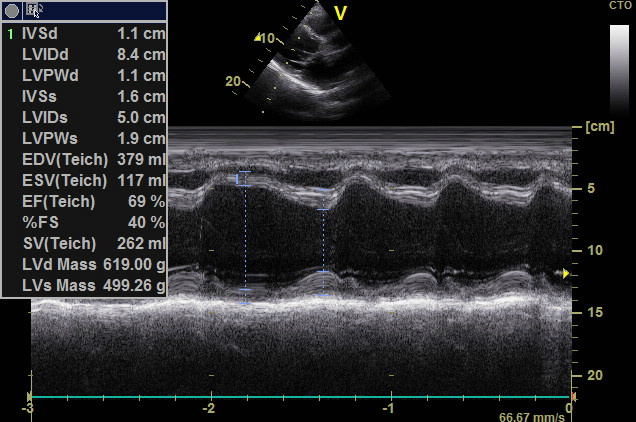

M-режим (M – motion) – режим одномерного сканирования с получением развертки в реальном масштабе времени, который применяется для регистрации пространственного положения исследуемых объектов во времени (отслеживания движения исследуемых структур).

М-режим, одномерный

Такой режим работы УЗИ обычно используют для проведения кардиологической диагностики. Он отображает на экране ткани сердечной мышцы в движении. Это даёт возможность оценить их упругость и эластичность.

М-режим был предпочтительным методом визуализации на заре УЗИ. М-режим определяется как отображение во времени движения ультразвуковой волны вдоль выбранной ультразвуковой линии. Он обеспечивает мономерное изображение сердца.

Все отражатели вдоль этой линии отображаются по оси времени. Преимущество М-режима заключается в очень высокой частоте дискретизации, что обеспечивает высокое временное разрешение, позволяющее записывать, отображать и измерять даже очень быстрые движения. Недостатком является то, что ультразвуковая линия закреплена на кончике ультразвукового сектора. Поэтому может быть сложно выровнять М-режим перпендикулярно отображаемым структурам (например, перегородке), что приведет к ложным измерениям.

Анатомический М-режим обходит это ограничение, реконструируя М-режим из 2D-изображения (постобработка). Анатомический М-режим позволяет свободно позиционировать линию курсора. Однако временное разрешение значительно меньше, чем у обычного М-режима.